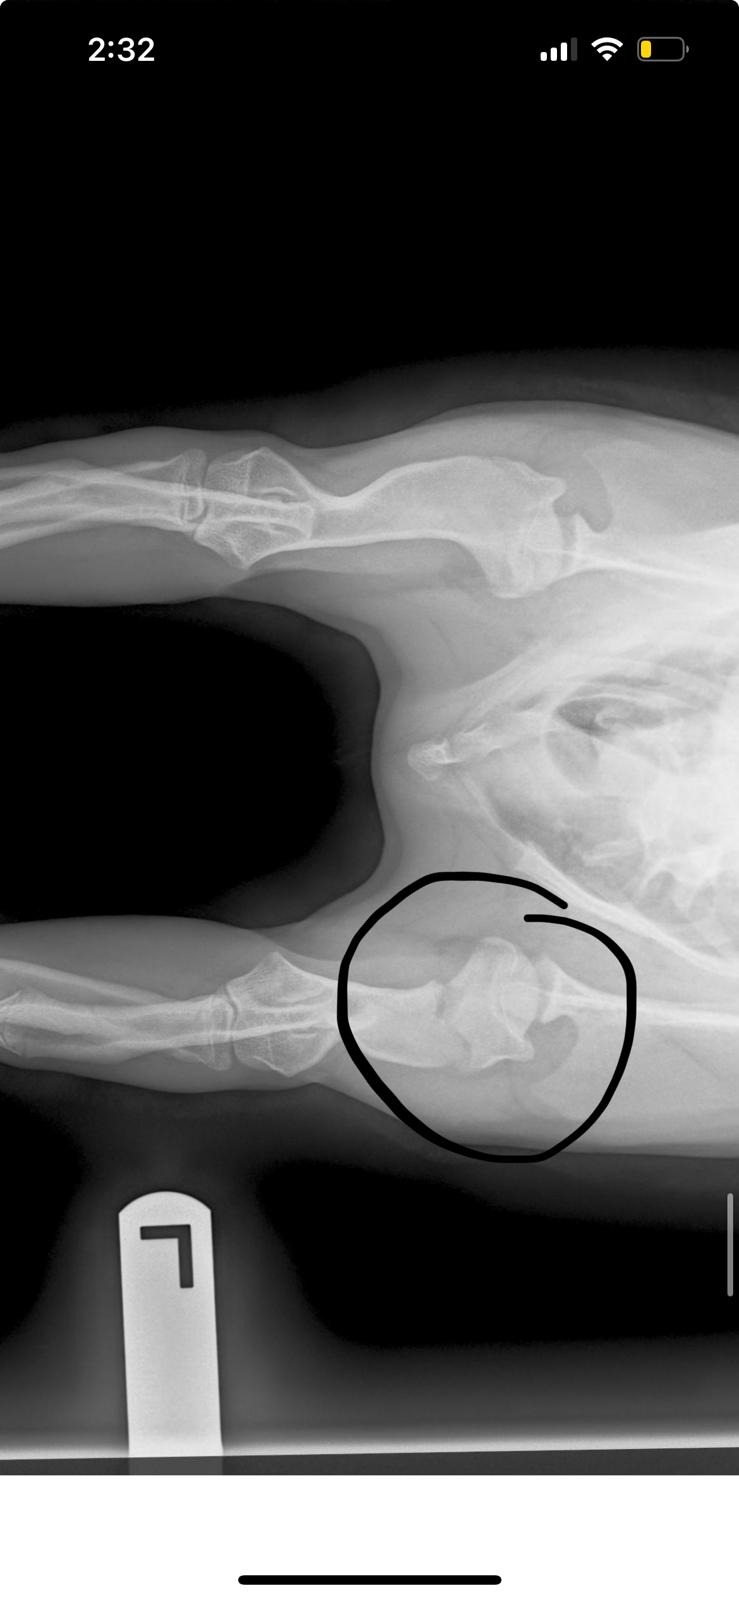

But while running in the park, Miso became frightened by another dog, fell, and broke her leg. She was lying there crying in pain. It was heartbreaking.

Miso now needs urgent surgery to repair her broken leg and give her the chance to heal properly and walk again without pain.